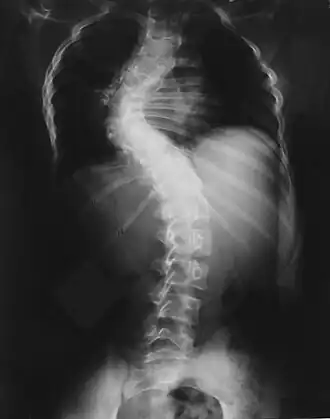

| Escoliose causada por recklinghausen | |

Pode causar lesões císticas nos ossos, geralmente danificando os metacarpos, falanges, ossos do quadril, fêmur e coluna vertebral. Quando causa compressão medular pode resultar em paraplegia [3] Foi descrita por von Recklinghausen em 1882.